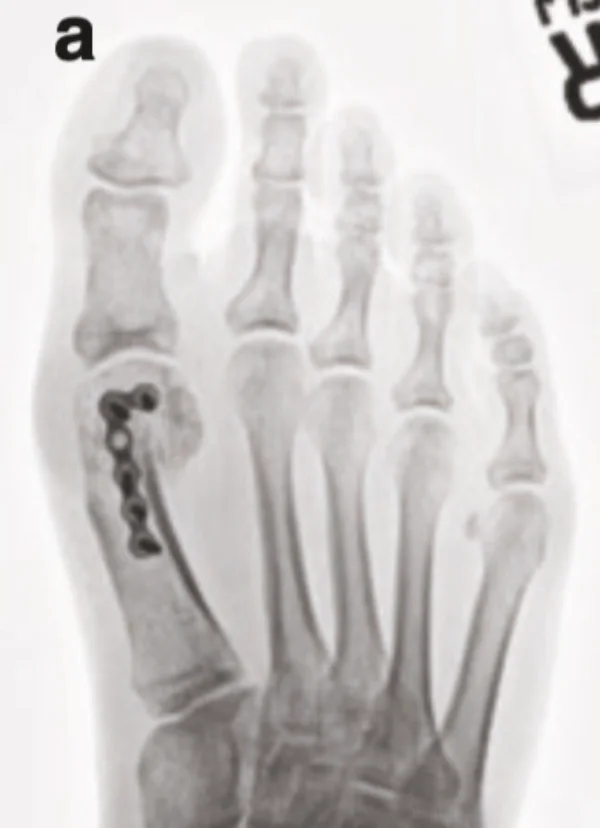

Scarf截骨术治疗拇外翻